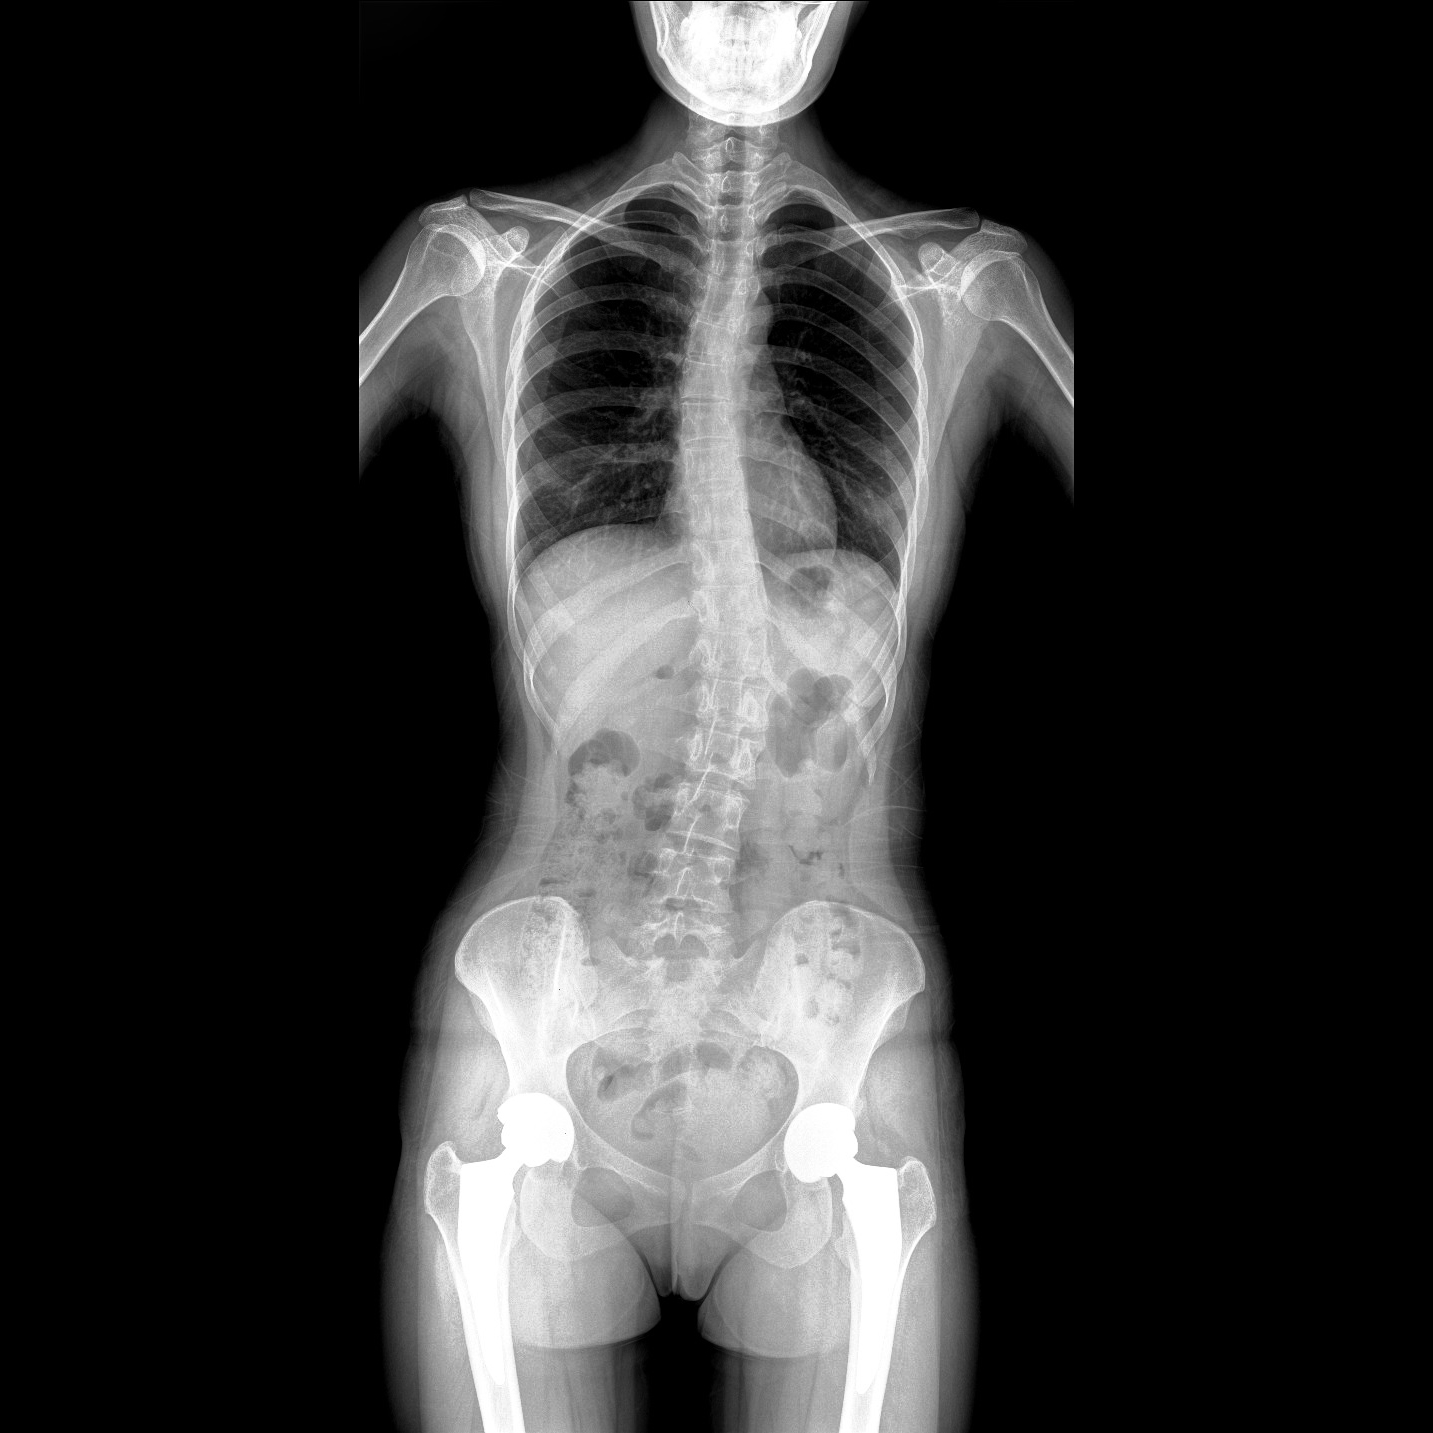

17"*34"有效視野,一次成像不拼接。相較于多張攝影再軟件拼接的DR設備,PLX8600解決了拼接圖像存在密度不均勻,拼接處圖像配準和放大效應等問題,給臨床帶來了大視野影像解決方案,可一次性覆蓋全脊柱或雙下肢影像。